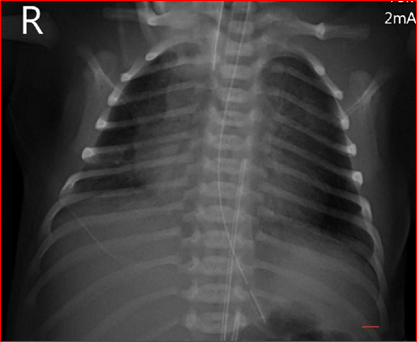

A repeat x-ray (Figure 2) including both chest and abdomen was performed on the following morning as the first X-ray did not demonstrate the whole course of both catheters. The second X-ray demonstrated that both the catheters were in the umbilical arteries. The catheter that ends at T10 (lower UAC) was catheterized via the right umbilical artery and the UAC that ended at T7 was catheterized via the left umbilical artery.

Figure 2 (Second X-ray: The two vascular catheters were identified as umbilical arterial catheters).